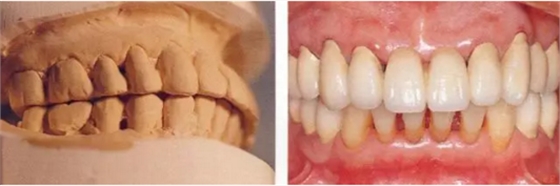

▲圖16-1~3

11.png

▲圖16-4

▲圖16-1~4 56歲,女性?;加腥谘乐苎浊蚁骂M磨牙區(qū)缺失,可以看到上頜前牙區(qū)有前突的現(xiàn)象。左上1和右上1無法保留。